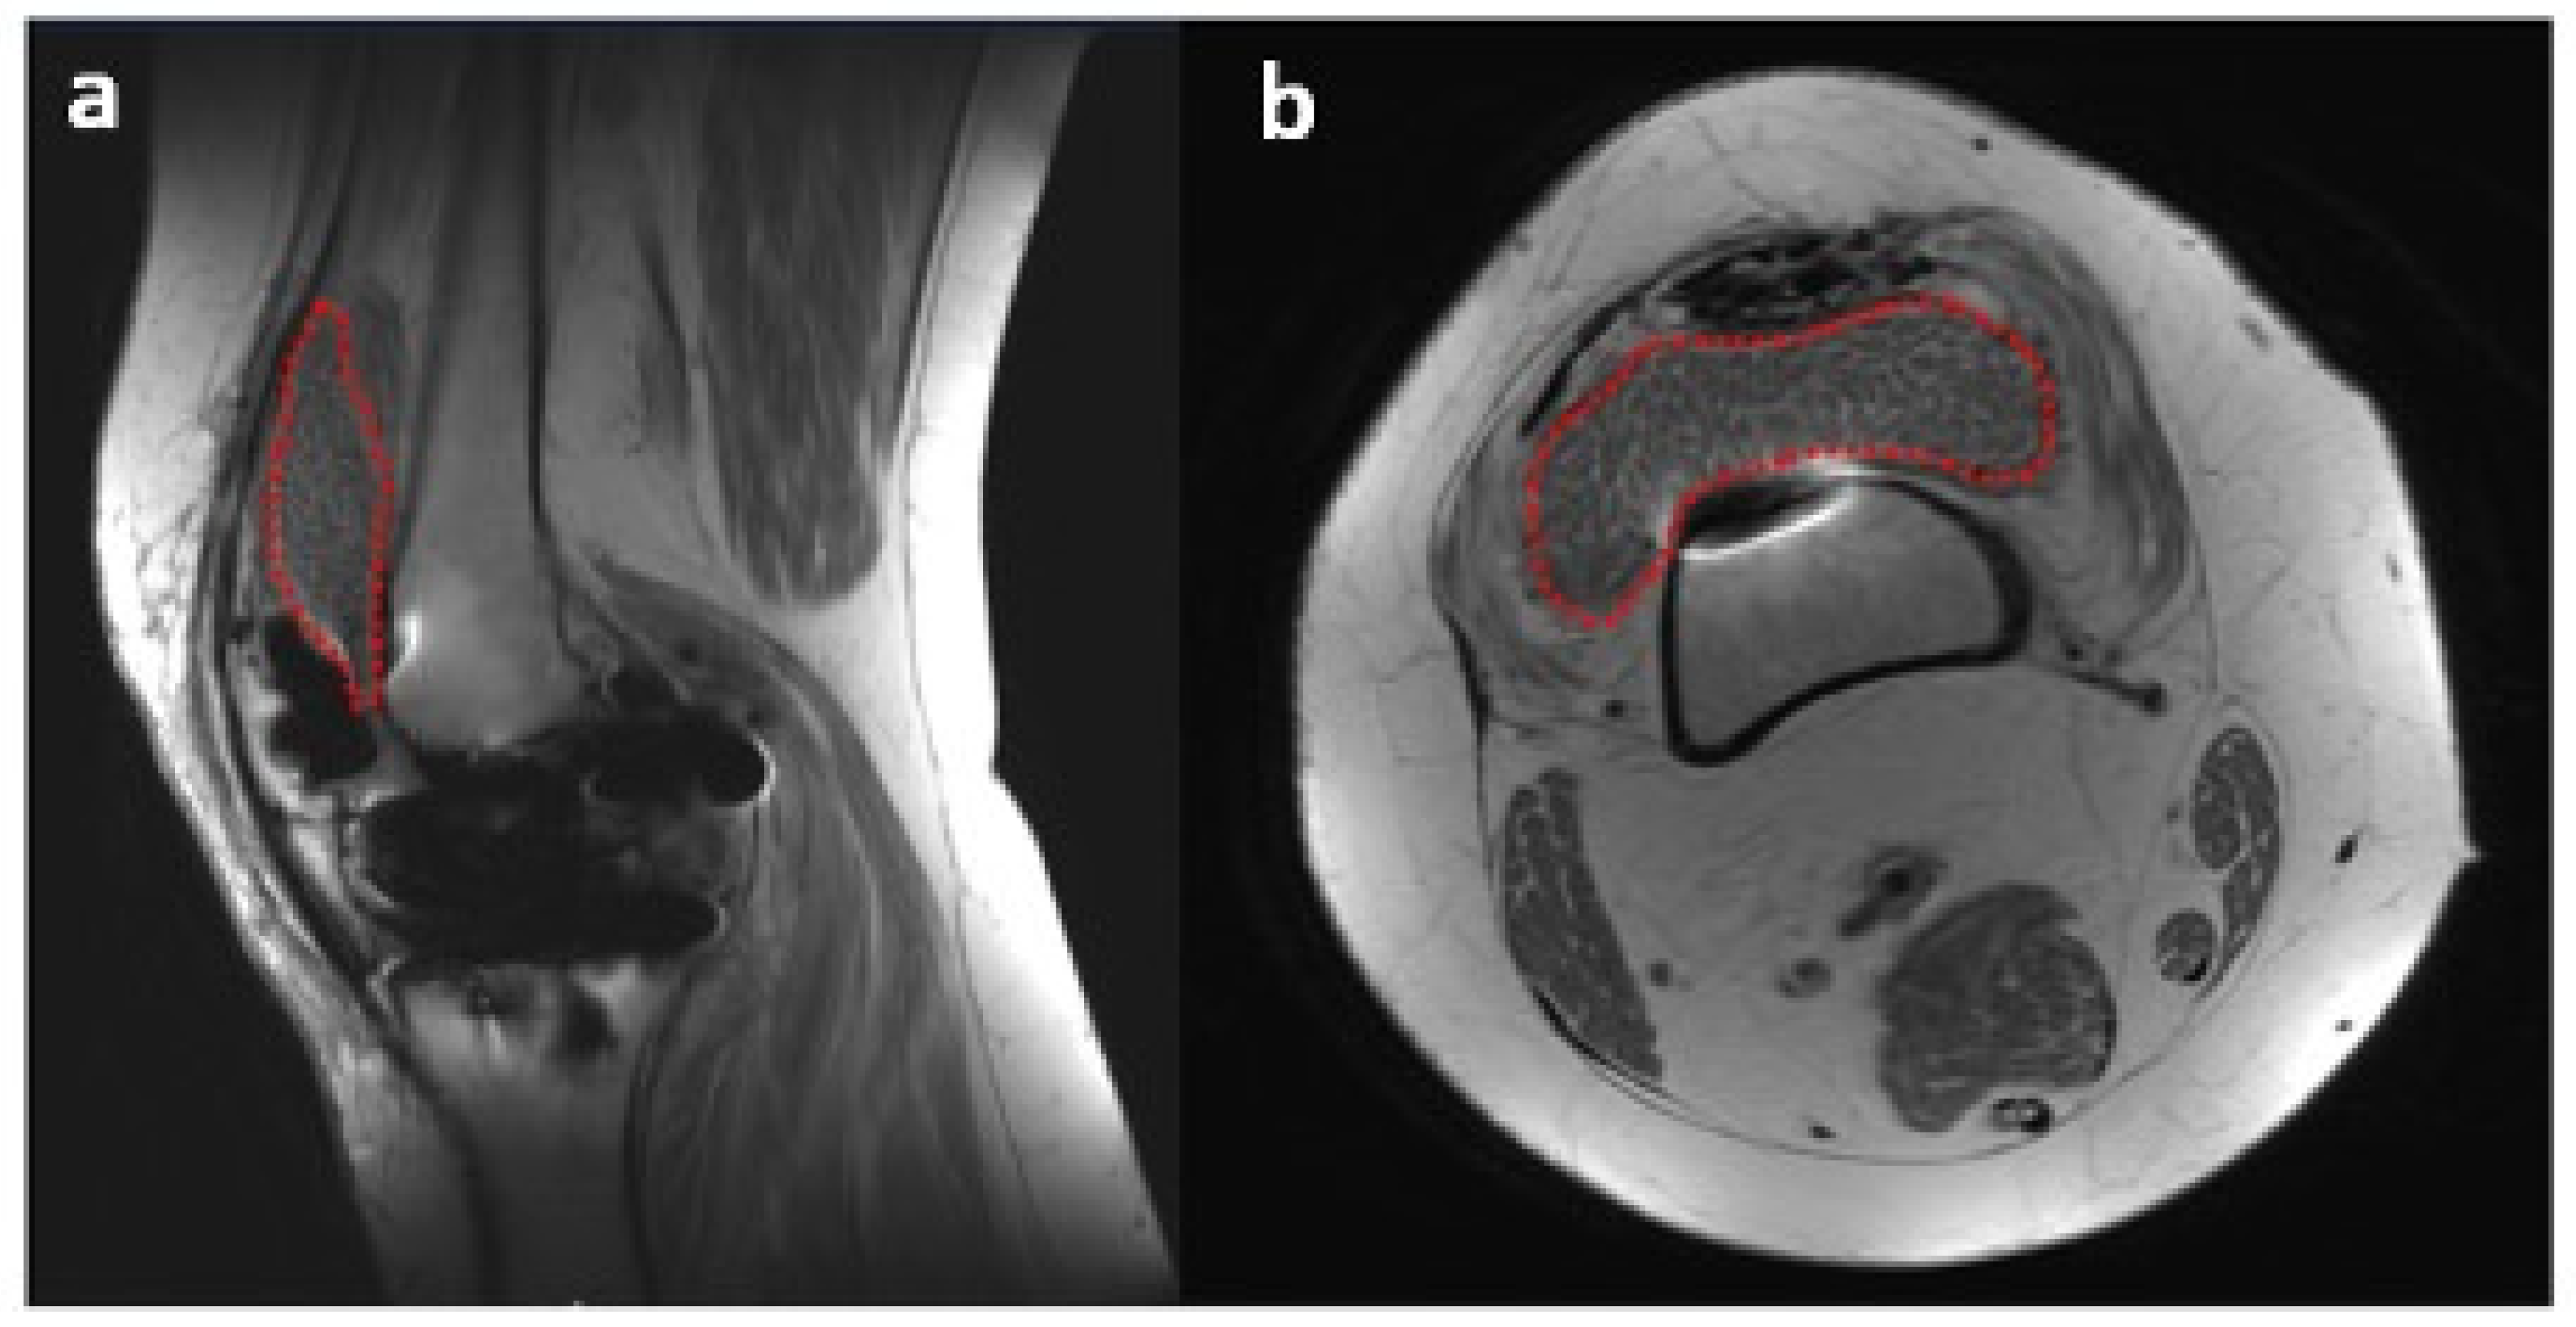

The suprapatellar pouch was found to be filled with a large number of smooth, white and loose rice bodies. The synovial fluid and rice bodies were collected for pathology and culture (Figure 4). The remaining loose bodies were excised from the knee using a grasper, arthroscopic shaver, and bipolar electrocautery. In addition to rice bodies, there were extensive synovitis and adhesions present, which were excised with a combination of an arthroscopic shaver and bipolar electrocautery. Given the patient’s need for anticoagulation due to a history of DVT and APS, care was taken to cauterize all possible bleeding sources within the knee. The implant interfaces were carefully examined, and they were all found to be well fixed. An arthroscopic synovectomy was performed, leaving the implants in place. A pathological examination revealed chondroid metaplasia covered by fibrin-like material (Figure 5). Upon careful histopathological examination by our pathologist, the structures that were originally identified as rice bodies were in fact small loose bodies from SC. This unusual case represents a rare instance where SC was initially mistaken for the more commonly seen rice bodies found in RA.

Figure 5. Microscopic display of a loose body after paraffin-embedded sectioning (a), hematoxylin and eosin (HE) stain, 20× magnification (b).